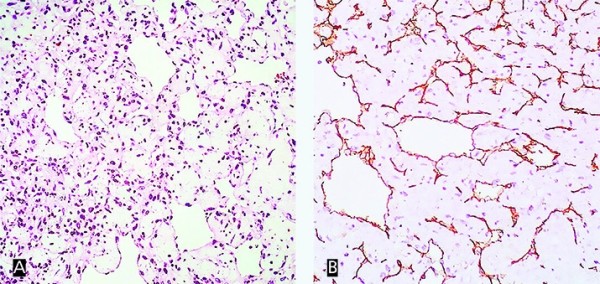

Рисунок 2. Капиллярная гемангиома. Окраска гематоксилином и эозином, увеличение× 200 (А). Иммуногистохимическая окраска CD31, увеличение × 200 (В).

Гистологическое исследование. Удаленное образование представлено множеством сосудов капиллярного типа в соединительнотканной строме с выраженным миксоматозом. В большинстве участков капилляры сдавлены, в других — сосудистые полости с папилломатозными разрастаниями в просвете. В строме скудная лимфоидная инфильтрация.

При иммуногистохимическом исследовании выявлено позитивное окрашивание на CD31 (маркер эндотелия), негативное окрашивание на D2-40 (маркер эндотелия лимфатических сосудов), негативное окрашивание на calretinin и S100 (для дифференциальной диагностики с миксомой).